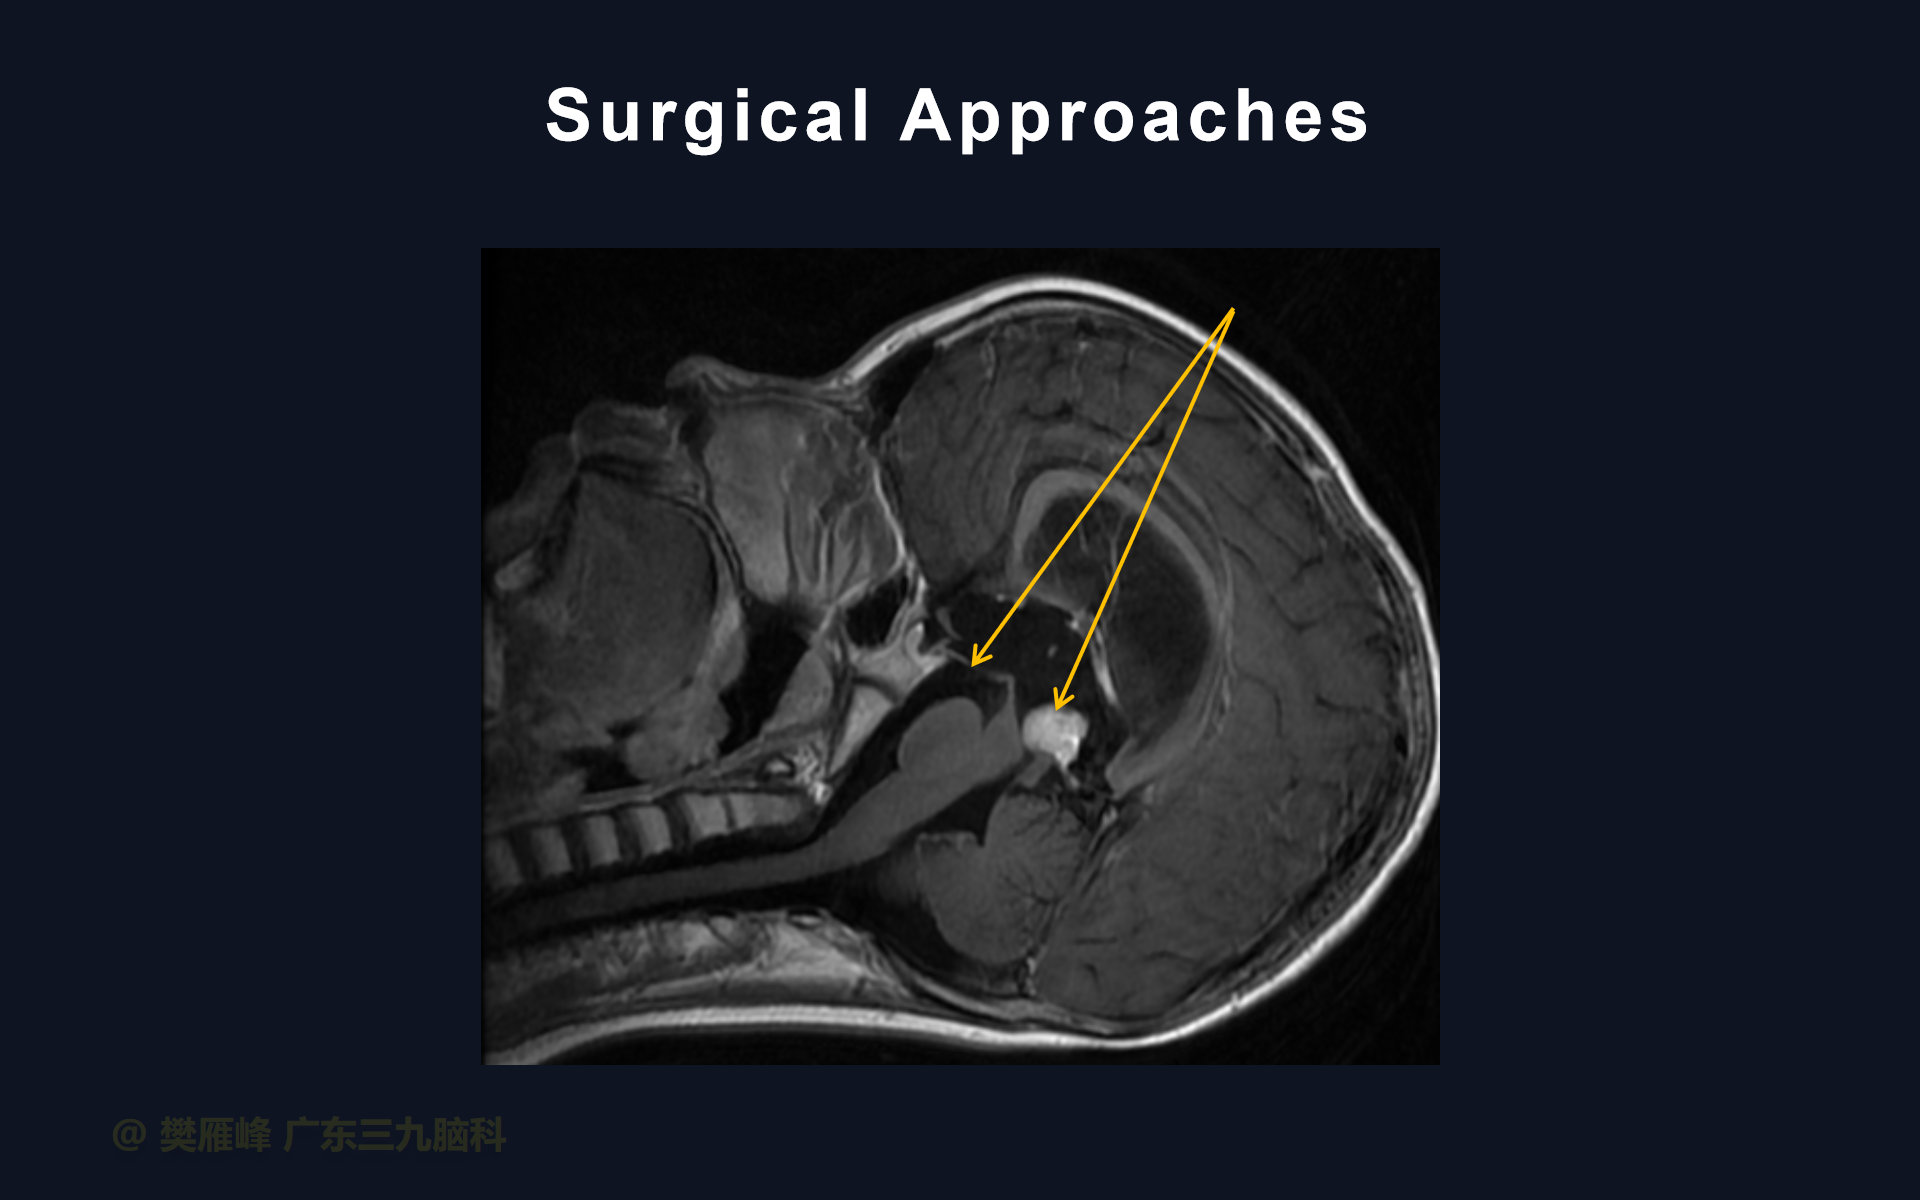

由于三脑室后部肿瘤患者的首发症状多为梗阻性脑积水引起,所以其治疗通常需先解决脑积水。对于非生殖细胞肿瘤,终极治疗手段为手术切除,应尽可能全切。但是,仅根据影像学和实验室检查往往难以在术前确定诊断。所以,组织病理学检查可帮助我们判断肿瘤是否需要全切,而对于那些不需要全切的肿瘤则可以避免积极手术带来的风险。

对于症状性脑积水,内镜下三脑室底造瘘优于脑室腹腔分流,可避免脑室腹腔分流引起的肿瘤细胞腹腔种植转移。然而,对于轻度或无症状的脑积水可不做特殊处理,因为肿瘤切除后脑积水一般自动解除。

第三脑室底造瘘时可同时行内镜下活检,这样,一次手术可处理脑积水获得病理诊断。

第三脑室后部肿瘤切除术前行ETV不仅有利于控制急性HCP,而且可以防止术后继发HCP的发生和最大限度地减少术后早期并发症。

在这个二维手术视频中,展示了2例神经内镜下三脑室底造瘘+活检治疗三脑室后部肿瘤的方法。患者均为三脑室后部病变导致的梗阻性脑积水,病理结果1例为生殖细胞瘤,1例为淋巴瘤,在经过术后的放化疗病情均得到控制,生活质量满意。我们展示了安全的病变活检和第三脑室造瘘的技术要点,以最大限度减少术后继发脑积水和早期并发症。